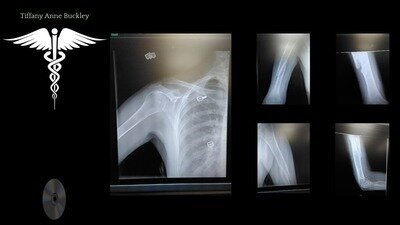

Physicians indicated within the reports, a spiral fracture of the humerus bone, yet markers indicate from the X-Rays that other areas, may have been affected and not included in the description of incidence. These photos are from 9 months post the original injury. Obtaining the ER Report from the date of incidence on 02/05/2023 and the radiology reports taken while in the state of PA, from Feb - Aug of 2023, is the reason for this request for support.